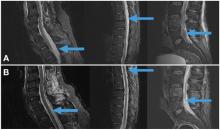

Síndrome de cola de caballo secundario a hernia discal

Resumen: el síndrome de cola de caballo (SCC) es  una entidad poco frecuente, provocado por la compresión de las raíces nerviosas en el canal a nivel de la cola de caballo. Puede dejar graves secuelas si no es diagnosticado y tratado de forma precoz. Únicamente 2% a 6% de las hernias discales lumbares van a provocar un SCC. El diagnóstico de esta patología se basa en criterios clínicos, siendo éstos objeto de controversia dada la variabilidad de presentación del cuadro clínico.